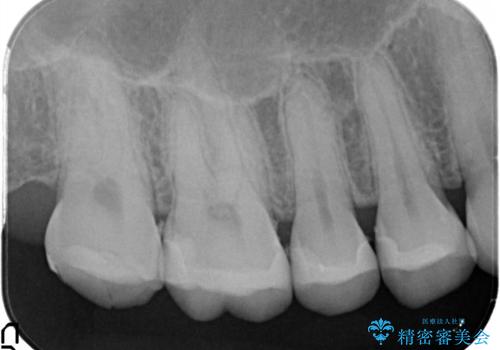

【メタルフリー】銀歯を白くしたい。オールセラミッククラウン。

- 銀歯を白くしたいと希望され来院されました。

すぐにでも白くしたいとのことで、2回目の来院で銀歯を白い仮歯に変更し喜んでいただきました。

ただ単純に白くするでけではなく拡大鏡を使用し、丁寧な処置を行なっております。